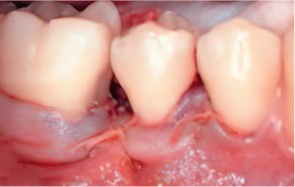

Emdogain Surgical Procedure

STEP 01

Gingival incision

-

STEP 02

Scaling and Root Planing (SRP)

STEP 03

Removal of calculus and plaque

STEP 04

Emdogain application

STEP 05

Cleansing

STEP 06

Flap closure and suturing